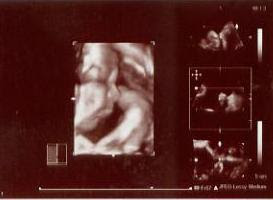

When I got back on the table, there was finally some progress! We could now see a bit more of his face since he'd moved his hands away slightly. He was opening and closing his tiny mouth and even stuck out his tongue twice... It was so funny! And we even got a smile! It was soooooooooooooo WONDERFUL!!! How I wished Je was there... he would have gone nuts over it.

I feel a lot more relaxed now after seeing our naughty baby last night, even if the most we were able to see was an oblique view of his face. Everything seems completely fine with him and with me. Except my doc told me to watch my diet because he's pretty big for his AOG. Apparently, my small bump belied what really lay beneath. It's mostly baby with just an adequate amount of fluid and a thin layer of fat. Oh NO! But I've definitely fallen equally in love with the new little man in my life. :o)

Here's a peek of our litsy bitsy baby boy. This is just a scanned copy of the polaroid shot because the CD copy comes after a week. They have to edit it and stuff. I'll post it once I have it.